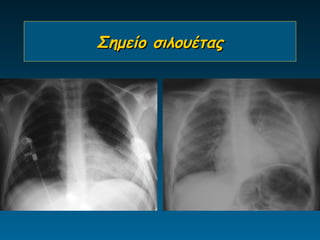

Σημείο σιλουέτας